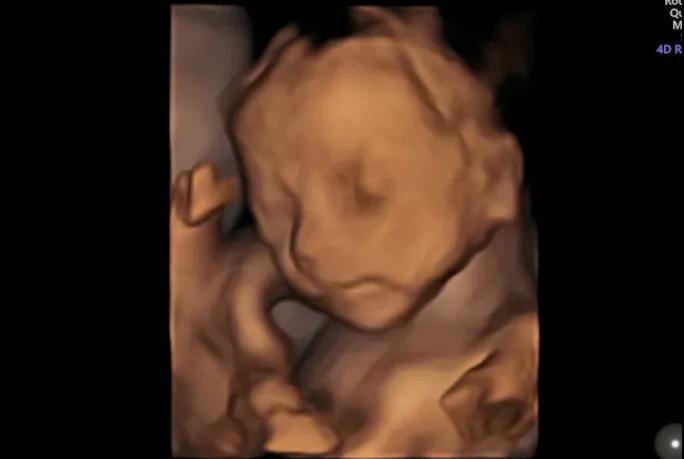

艾玛妇产的超声影像拥有独立的诊室,双彩高清显示屏,不仅能让来做检查的宝妈可以看到宝宝,陪同的家属同样可以起近距离观察宝宝的举动;

医生在做筛查时还会抓取部分照片和视频片段赠送给宝爸宝妈以作留念。